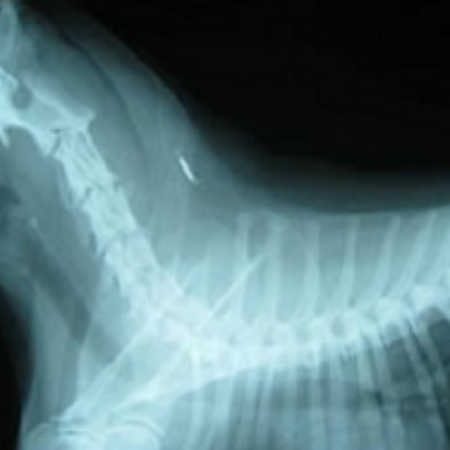

レントゲン画像

首の後ろにマイクロチップが写っています